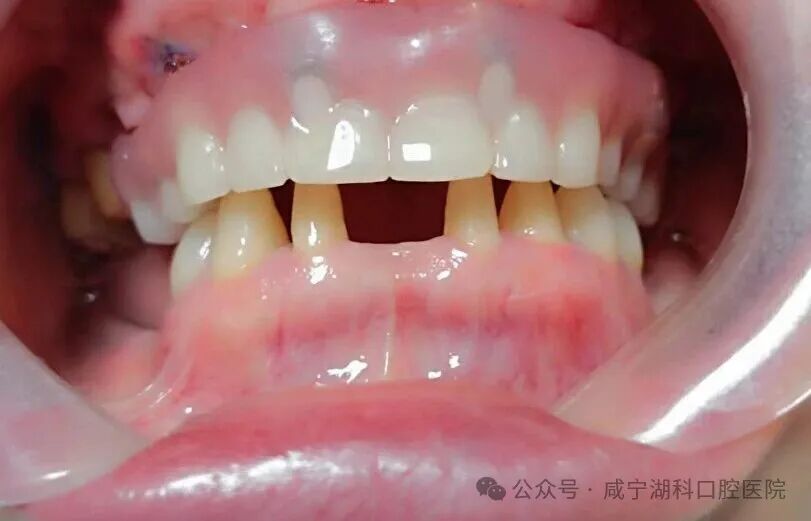

“想做种植牙,但是他们说我牙槽骨太薄,已经没办法再种了。”胡阿姨回忆道,此刻,她的口腔内,上颌仅剩4颗牙,下颌磨牙全部缺失,严重影响了进食和社交,生活品质一落千丈。

刘伟院长根据胡阿姨的牙齿情况,分析到上颌窦剩余骨量非常少,做种植有两种方式,一种是采用上颌窦外提升,需要大量植骨,要忍受大半年至一年的无牙期,而且要进行两次手术才能完成修复。第二种是穿翼种植,是一种新技术,目前咸宁掌握这项种植技术的医生很少,这项技术是拔完牙后即刻就进行穿翼种植,只用一次手术就能完成种植,当天就能戴牙,大大缩短修复时间,减少无牙痛苦。

经过多方比较,1月25日,胡阿姨最终选择了刘伟院长为她进行穿翼种植,最终当天拔掉上颌两颗松动牙,保留了2颗大磨牙,植入5颗种植体,当天拔牙当天种当天戴固定牙。她说:“毕竟湖科口腔口碑很好,种植牙是很考验医生技术的手术,既然要做,就要找靠谱的、术后维护有保障的医院,技术过硬的医生。”

在这种手术中,种植体不是常规地植入牙槽骨,而是穿过上颌窦,把种植体植入到鼻部两侧的翼骨。翼状板位于上颌骨后部,较为坚固,能够提供良好的支撑。这就像是为牙齿的修复搭建了一个超级稳固的 “桥墩”,为牙列缺失或严重损坏的患者提供了一种有效的解决方案。